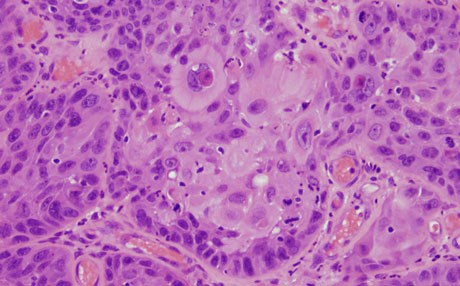

ئەمانە هەندێك نیشانەن، كە ئەگەر هەبن، پێویستدەكات راوێژ بە پزیشك بكەی سەبارەت بە هەبوونی شێرپەنجەی چووك:

1-برینێك لە چووك كە دوای 4 هەفتە ساڕێژ نەبێ. برینەكە رەنگە شێوەی جیاوازبێ هەر لە تلۆق و برینی تەڕەوە تاكو شێوە بالووكە